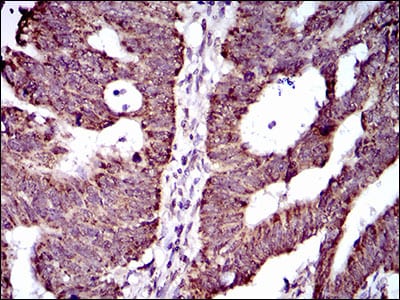

- Immunohistochemical analysis of paraffin-embedded human cervical cancer tissues using ABCG5 mouse mAb with DAB staining.

- Immunohistochemical analysis of paraffin-embedded human rectum cancer tissues using ABCG5 mouse mAb with DAB staining.